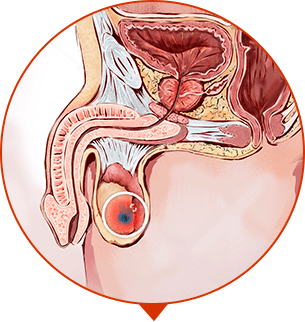

¡PONTE A PRUEBA! PRÓDROMOS DE LA PROSTATITIS:

Una vez al año/medio año Usted ha sentido el dolor tirante en la zona de la ingle

A veces Usted siente punzadas, presión en la ingle

Usted se ha dado cuenta de miccionar más a menudo

Ve que un testículo está más bajo que el otro

De vez en cuando Usted sufra por el estrenimiento o diarrea

Ve que la erección se ha vuelto más débil

Se ha bajado la libido

Aunque una vez Usted ha tenido problemas con la micción

¡SI USTED HA DESCUBIERTO EN SÍ AUNQUE UN SÍNTOMO, COMIENCE URGENYE EL TRATAMIENTO!

Usted sufre por el dolor. La prostatítis no le deja vivir. Es posible que Usted se sienta peor aun en los próximos 1 o 2 años. La infertilidad. La sangre a la hora de eyacular y miccionar. La estasis de la orina en la vejiga (hasta 500 ml). La vesiculítis.

IMPOTENCIA

Impotencia sexual incurable

ADENOMA DE PRÓSTATA

Crecimiento excesivo del tejido de la próstata, formación del tumor y “nudos”

ONCOLOGÍA

Tumor maligno, la causa más frecuente de la muerte de los hombres